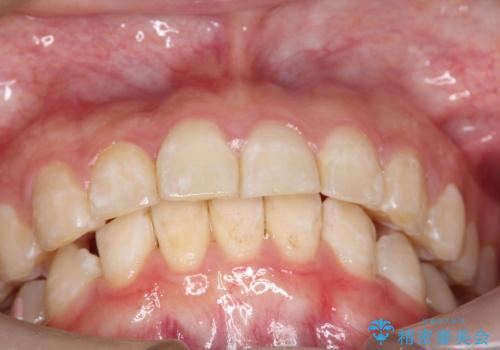

[ インビザライン ]飛び出た前歯を抜かずに矯正治療

担当医 大元洋佑